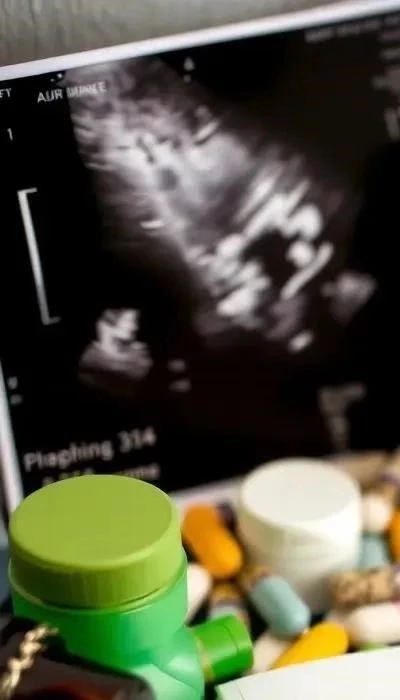

Тщательный мониторинг состояния плодов с помощью УЗИ и КТГ позволяет своевременно выявлять признаки гипоксии и принимать меры для ее коррекции. Важно помнить о необходимости регулярных обследований и соблюдения всех рекомендаций врача.

2. Диагностика и скрининг многоплодной беременности

Диагностика многоплодной беременности обычно начинается с ультразвукового исследования (УЗИ). Первое УЗИ, как правило, проводится в первом триместре, и именно оно позволяет подтвердить наличие нескольких плодов. Последующие УЗИ проводятся регулярно для мониторинга роста и развития каждого плода.

Анализы крови играют важную роль в оценке состояния матери и плодов. Регулярно контролируются показатели гемоглобина, глюкозы, а также проводится скрининг на наличие инфекций. Скрининги первого, второго и третьего триместров при многоплодной беременности проводятся по специальной схеме, учитывающей повышенные риски.